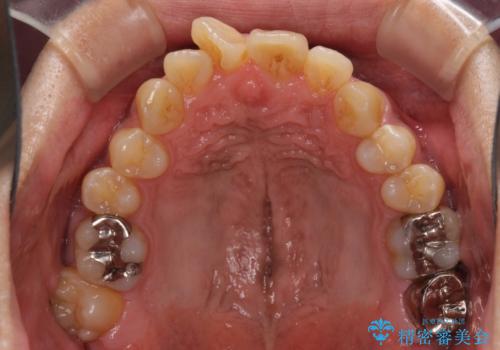

上顎の狭い歯列をインビザラインで拡大

- 上下前歯の叢生を気にして来院された患者様です。

奥歯はクロスバイトとなっているので上顎は側方拡大を行いつつ、上下全体の叢生をインビザラインにより改善することとしました。

治療途中でクリーニングやホワイトニングを行い、歯列が整うと同時に明るい口元となりました。